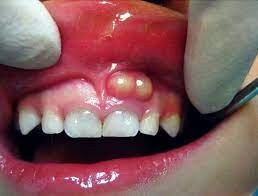

What Is A Tooth Abscess?

A tooth abscess is a bacterial infection found in the inner part of the tooth where pus has collected and can cause moderate to severe pain in people who suffer from the condition. Tooth abscesses can occur when a cavity has gone untreated for too long or when a crack or chip in the tooth allows bacteria to find its way into the dental pulp (the inner, soft part of the tooth) area of the tooth and gets infected.

Once the bacteria has made its way inside, it will spread down to the root and cause both inflammation and swelling. Once inflammation occurs, it will force the pus into a tight space (known as the abscess) at the tip of the root where the swelling exists.

Symptoms

Signs and symptoms of a tooth abscess include:

Persistent, throbbing or severe toothache

Extreme temperature sensitivity

Pain when performing normal chewing or biting

Fever

Swelling in the face or the cheeks

Lymph nodes under the jaw or in the neck become tender or swollen

A rush of foul-tasting fluid in the mouth followed by cessation of pain, which means the abscess has ruptured

When Should You Consult Your Dentist?

If you experience any of the signs or symptoms listed above, you should see your dentist immediately, especially if you begin to experience swelling in your face or begin to feel feverish. If your dentist cannot see you immediately, you should go to an emergency room as it’s possible these symptoms indicate the infection is possibly spreading into your jaw and the surrounding tissue.

The only way to rid yourself of both the pain and the condition is to get proper dental treatment. You may feel a lessening of pain if the abscess ruptures, but you’ll still need to get a professional’s help. The infection could spread to other parts of your jaw and beyond to parts of your head and neck and, in a worst-case scenario, lead to sepsis, which is an infection throughout the entire body that can put your life at risk.

Testing and Diagnosing

Beyond regular dental checkups, your dentist may perform a couple of specialized tests to confirm you have an abscessed tooth:

Tooth Tapping — An abscessed tooth is often very sensitive to touch or pressure, so your dentist may apply both to the tooth in question to determine your pain levels.

X-rays — An X-ray, or other imaging test (such as a CT scan), can help identify an abscess, so your dentist may require taking some to be sure.

Lab Tests — If the first line of antibiotics doesn’t help combat the infection, your dentist may take a sample of the infection to find out what kind of bacteria is causing it. This will help pinpoint a more effective treatment plan moving forward.

Tooth Abscess Treatments

Treating a tooth abscess involves draining the abscess and ridding the area of the infection. The tooth itself may be saved with a root canal treatment, but in some instances, it may need to be removed completely. Leaving a tooth abscess untreated can lead to serious, even life-threatening, complications. Your dentist or oral surgeon may recommend the following:

Root Canal Procedure — If possible, your dentist will try to save your tooth by performing a root canal. The tooth is cleaned and disinfected on the outside, drilled into and cleaned out from the inside and then filled with a safe adhesive cement to restore structural integrity (and protect the tooth from future infection). If taken care of, this restored tooth will last your entire lifetime.

Extract or Pull the Affected Tooth — Extracting the tooth is a last resort, but if the tooth cannot be saved, your dentist will elect to choose this option to preserve the health of the rest of your mouth. Once extracted, the abscess will be fully drained and cleaned to prevent further infection.

Antibiotics — If the infection is localized around the abscessed area, you may not need antibiotics. However, if the infection has spread beyond it, your dentist will prescribe antibiotics to help slow or diminish the infection, especially if you have a weakened immune system.

While the area is healing, your dentist may recommend that you regularly rinse your mouth with warm salt water and take over-the-counter pain relievers as needed to help ease any discomfort you may encounter.